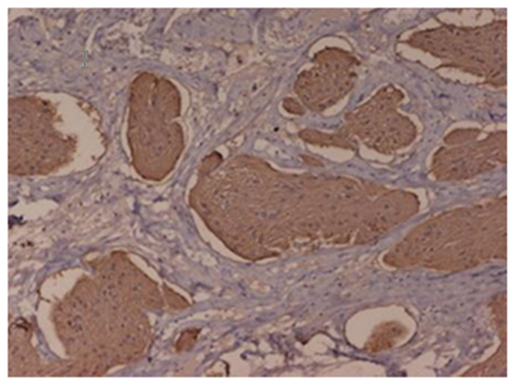

Photos of Glioma Recurrence

Glioma Recurrence Images

Glioma Recurrence Photos

Images of Glioma Recurrence

Glioma Recurrence Pictures

Pictures of Glioma Recurrence